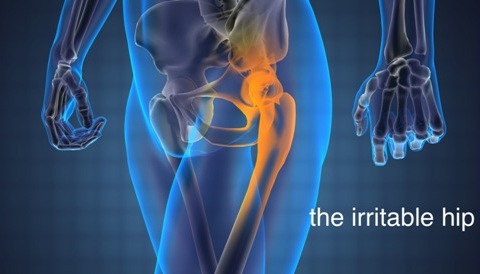

ΤΙ ΕΙΝΑΙ Η ΥΜΕΝΙΤΙΔΑ ΤΟΥ ΙΣΧΙΟΥ

Υπάρχουν πιθανά δύο είδη επώδυνου ισχίου. Το πιο συνηθισμένο προκαλείται από συλλογή υγρού στην άρθρωση του ισχίου το οποίο εμποδίζει την καλή λειτουργία της άρθρωσης. Το υγρό μπορεί να εύκολα με υπερηχογράφημα ισχίου, αν και η κλινική εικόνα είναι συνήθως αρκετή.

Το δεύτερο είδος προέρχεται πιθανά από φλεγμονή λεμφαδένων στην κοιλιακή χώρα από ίωση.